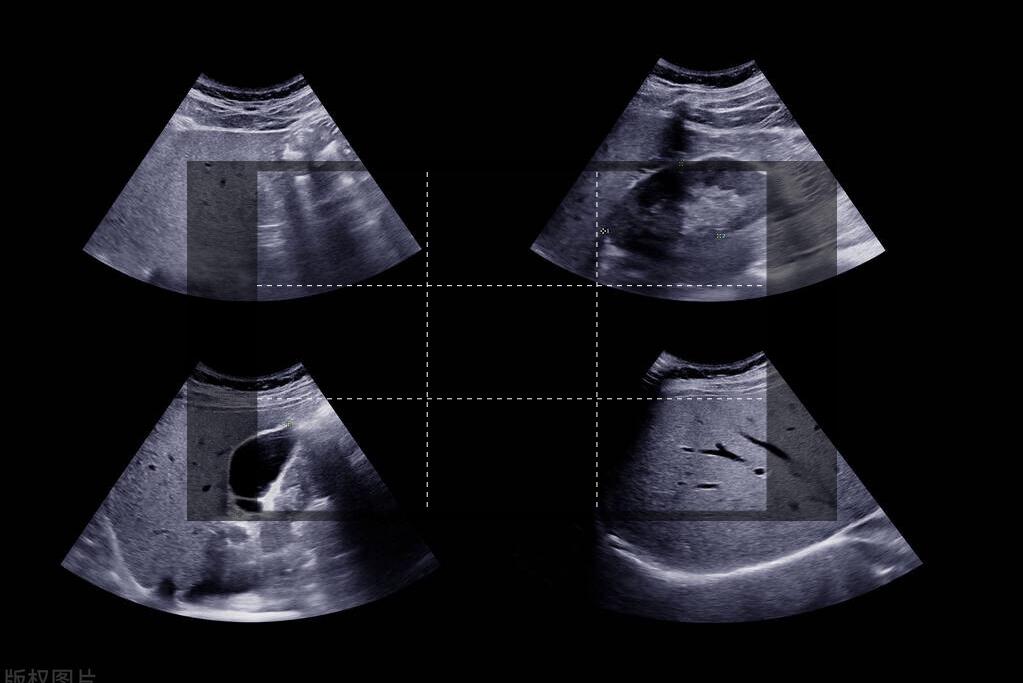

前段时间,王姐总是感觉自己腹部有疼痛感,还总是觉得肚子胀胀的。这种症状维持两个月后,王姐实在忍不住了,去医院进行彩超检查。

检查结果出来后,王姐吓了一跳,医生竟然说她的胆囊内长了一个瘤。好在这个瘤是良性的,手术切掉即可。但是这一疾病的诊出还是让王姐心有余悸。